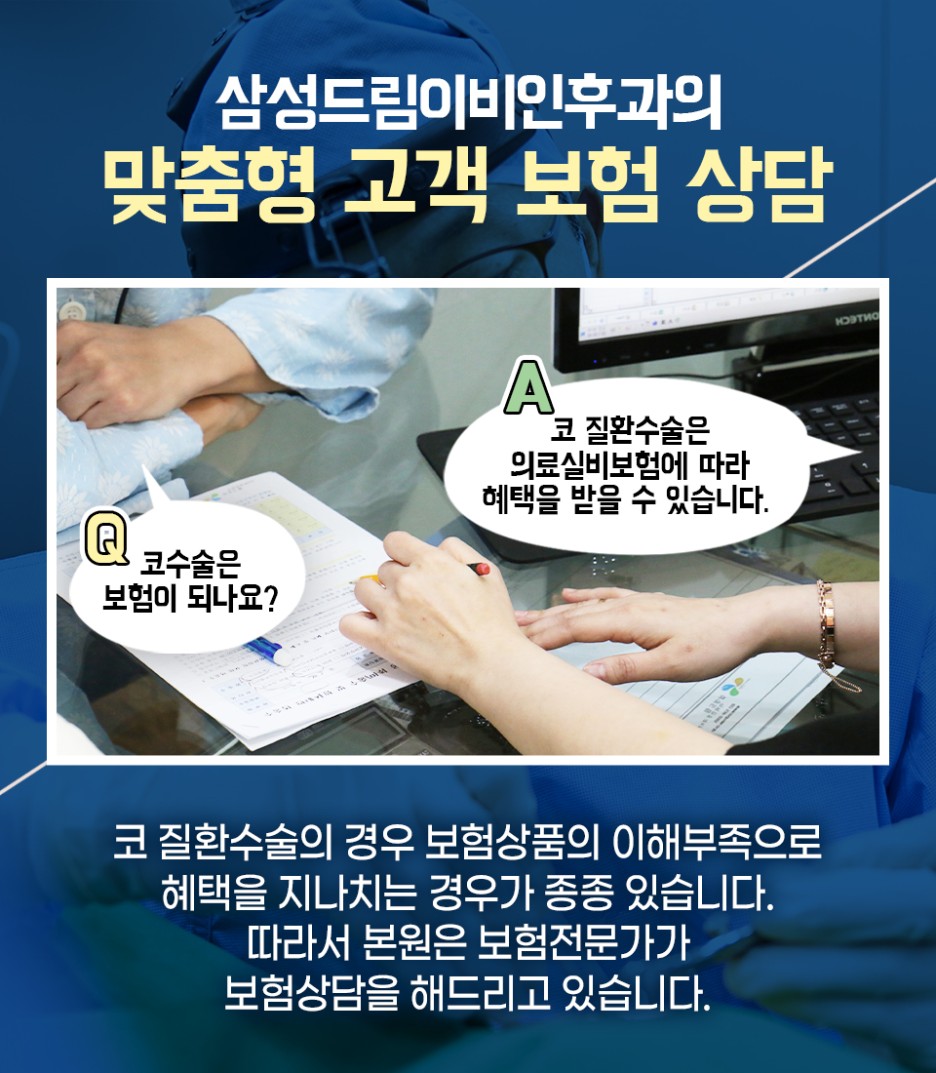

축농증 수술 후에 확인을 해도 걱정이 되는 분들이 많이 계셨습니다. 원인은 각각 다양한 종류가 있지만 일반적으로 비용 걱정이라고 할 수 있습니다. 대부분의 생활에서 경험할 상황이 아니기 때문에 부담감이 있을 수밖에 없다는 게 사실이었어요. 비용 걱정은 실비 보험이 적용되기 때문에 어느 정도 부담감을 낮출 수 있었습니다.

코는 외형적으로도 미적인 요소개선의 목적이라면 실비보험이 적용되지 않지만 축농증과 같은 코의 기능개선과 치료목적으로 접근하여 실비보험이 적용 가능하므로 충분히 고려할 수 있었습니다. 그러나 보험에 따라 보상 약관의 차이가 있기 때문에 걱정하시는 분들도 많았는데요. 이런 내용까지 고려할 필요가 없었어요.

저희 병원의 경우 보험에 관해 걱정하지 않도록 충실한 도움과 대화를 하고 있었습니다. 또 다른 축농증 수술 사례를 확인하고 이를 극복하려는 분들이 계시기 때문에 시간적 여유 부족, 그리고 침낭이기 때문에 고민하시는 분들도 많으실 텐데요. 그럴 필요 없이 비교적 빠른 시간 내에 수술과 회복이 진행되기 때문에 스케줄 부담감도 낮출 수 있었습니다.